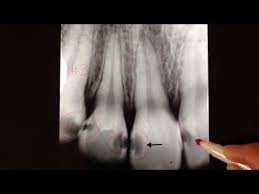

- رادیو لوسنسی از اپکس به سرویکال = اندو اولیه

- رادیولوسنسی از سرویکال به اپکس= پریو اولیه

- پاکتِ کَمَر باریک = اندو اولیه

- پاکتِ کَمَر پهن = پریو اولیه

- رادیولوسنسی فورکا = اندو اولیه